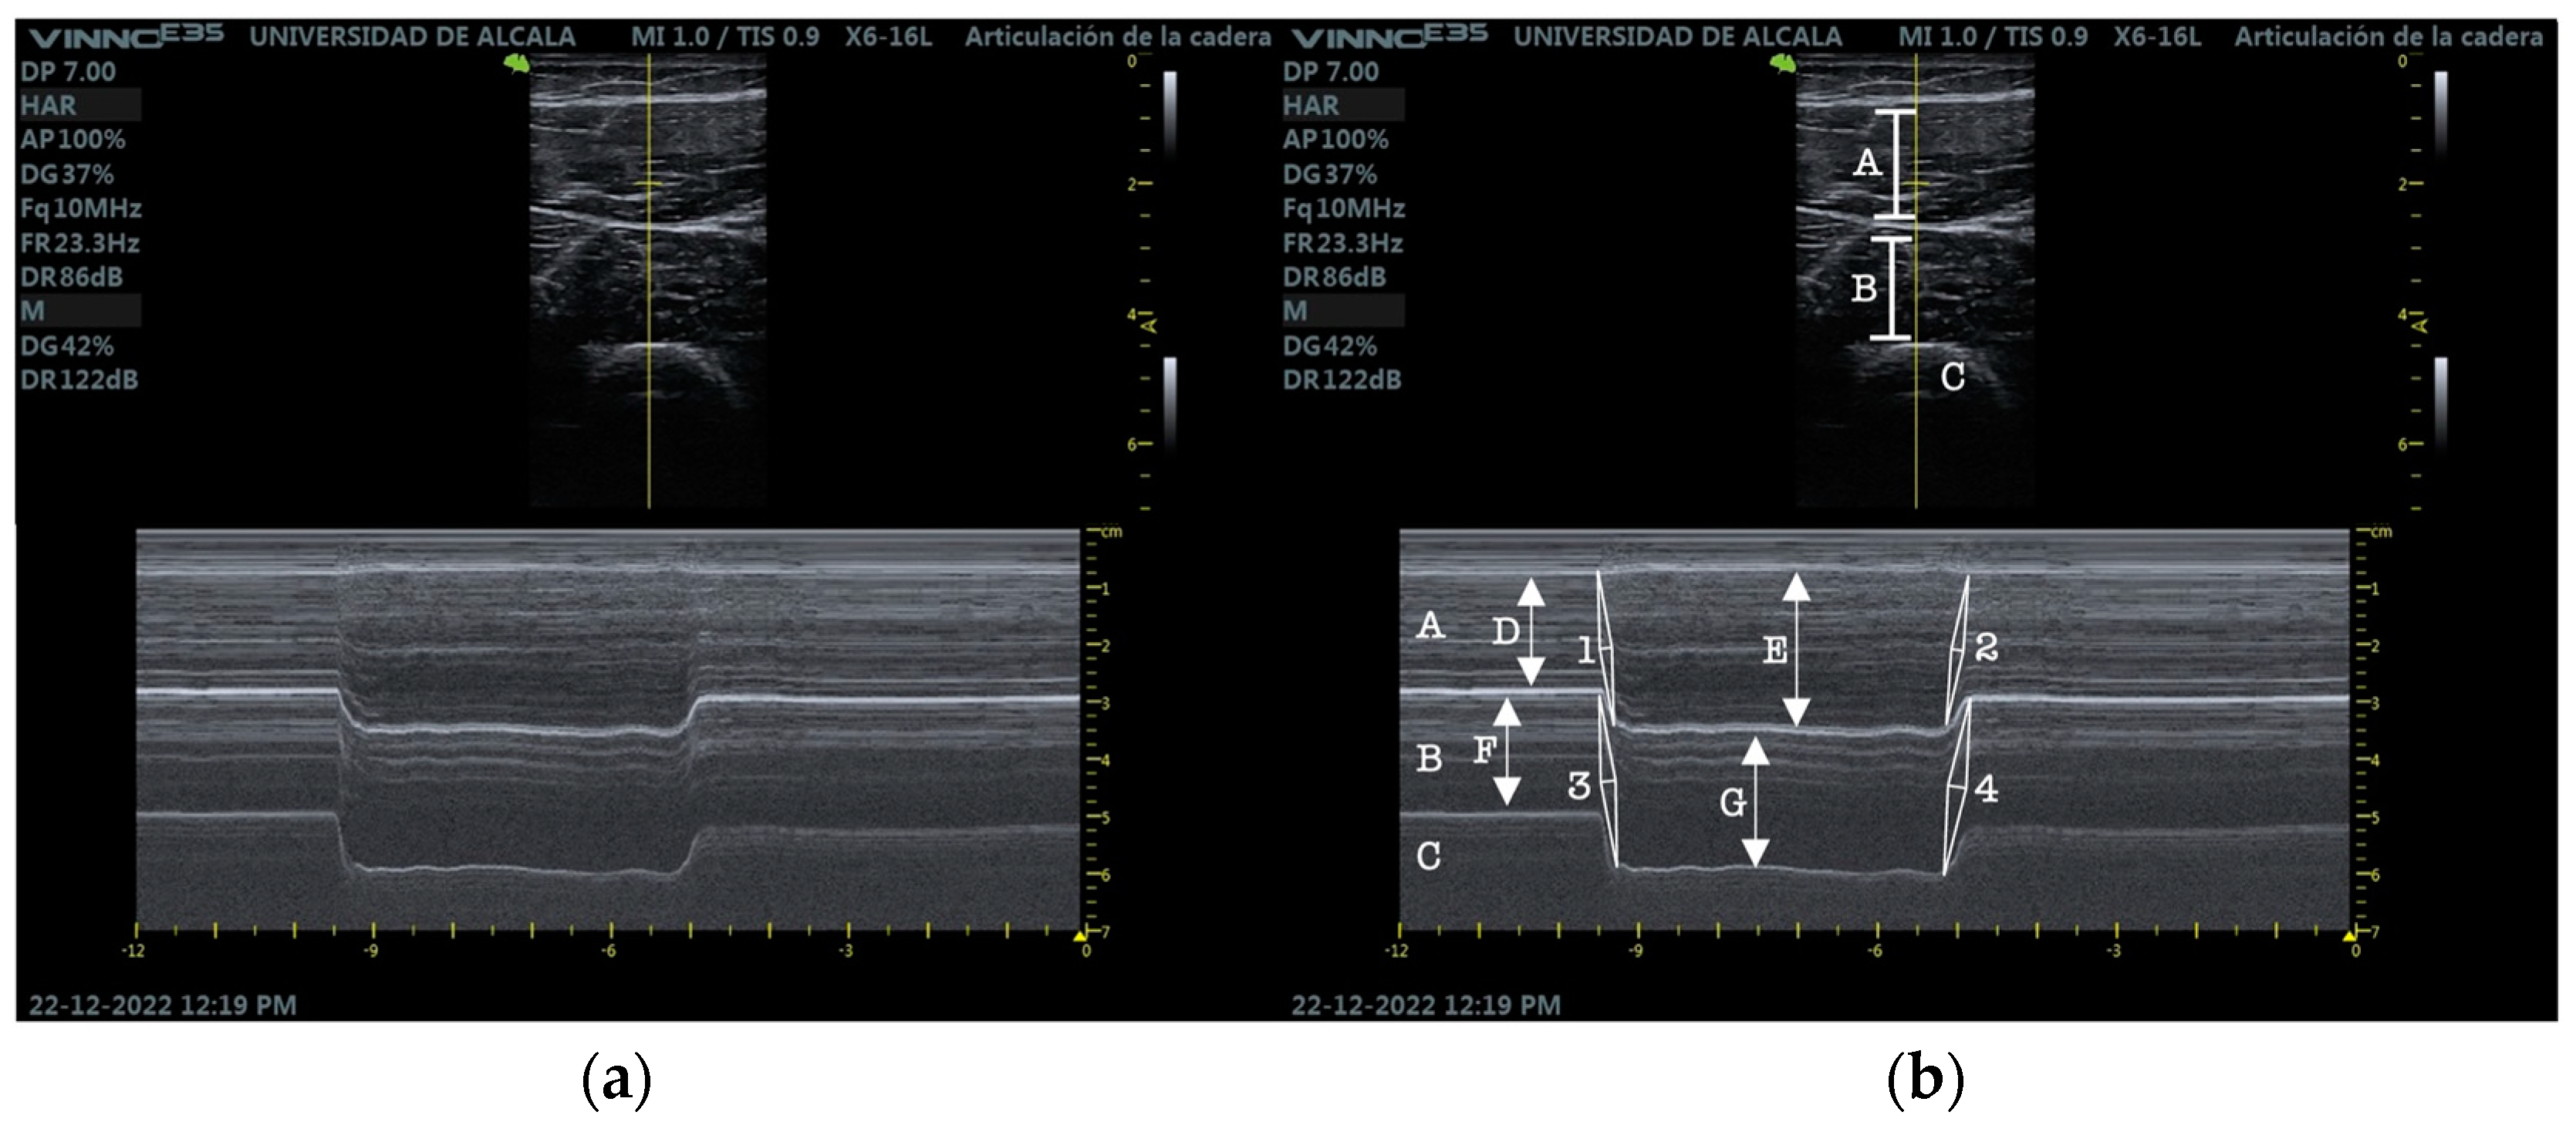

2.5. RUSI Measures